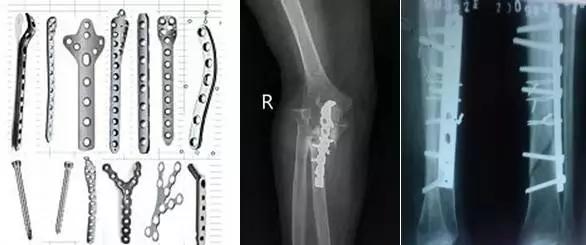

骨科内固定材料

骨科内固定材料主要有不锈钢系列、钴铬钼合金、钛和钛合金等。目前所用的较新的内固定材料多由纯钛或钛合金制成,与磁场没有相互作用,在磁场中不会移动,可以行磁共振检查,但仍可能出现伪影的问题。

而较老的不锈钢等材料的内固定物,由于材料在强大磁场中可能发生移动而损伤邻近大血管和重要组织,产生严重后果,一般是磁共振检查的相对禁忌证。产生伪影的问题,钛金属略微优于不锈钢材质。患者事先一定要和医师充分沟通后才能确定最佳植入材料和最适检查方法。